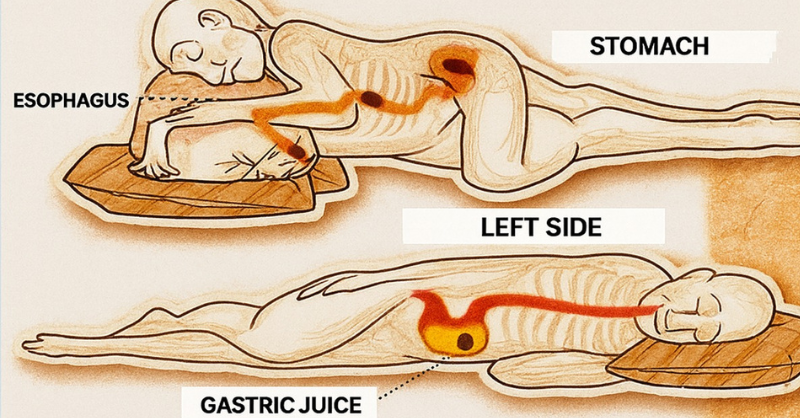

This is what sleeping on the left side does for our brain, stomach & glymphatic health

Most of us have a go-to sleeping position—but what if the way you sleep is quietly influencing your health? While side sleeping is already popular, lying specifically on...